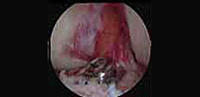

Tratamiento de las fracturas de rodilla con técnicas artroscópicas

En ocasiones en la práctica deportiva, principalmente esquí y snowboard, se producen fracturas a nivel de la rodilla que requieren un tratamiento quirúrgico. En la actualidad el uso de la cirugía artroscópica permite realizar la intervención quirúrgica con mínimas incisiones lo que conlleva menores molestias postoperatorias y una recuperación más rápida para el paciente.

Tenemos una larga experiencia en el tratamiento de estas lesiones y hemos incorporado los últimos avances en cirugía para obtener un resultado más favorable y con menores complicaciones para el paciente.